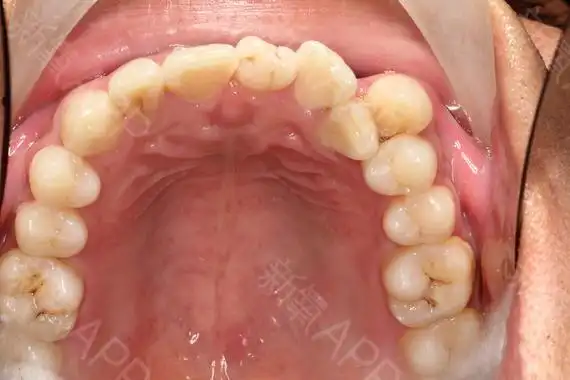

这是什么情况,口腔壁长泡能自愈吗

口腔上颚疼痛起泡,总感觉里面好像有水一样舌头顶着会动感觉痛到神经

口腔内部照片很清晰

口腔内部高清晰图片

正常口腔黏膜及常见病损图